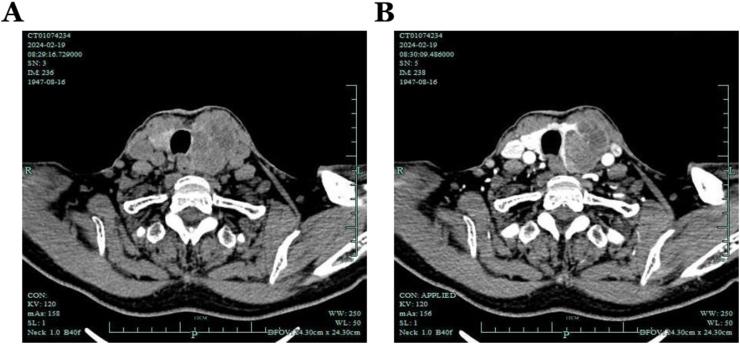

A 76-year-old female presented with a giant neck mass. Physical examination revealed a large, firm mass in the left thyroid gland. No symptoms such as hoarseness or dysphagia were noted at the time of presentation. The patient underwent unilateral thyroidectomy and cervical lymph node dissection.